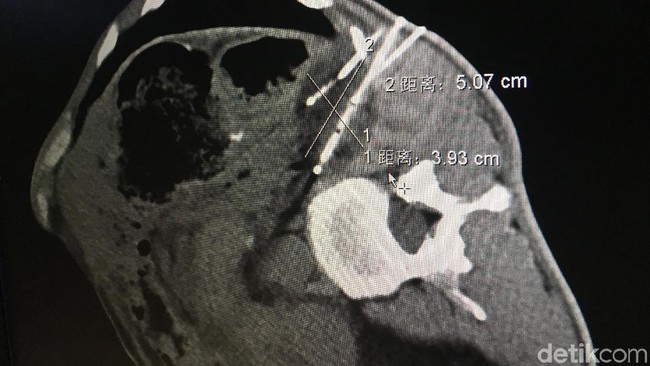

Salah satu penyebab tingginya angka kematian tersebut adalah karena sulitnya diagnosis kanker paru-paru dini. Sekitar 40% penderita kanker paru baru mendapat diagnosis setelah penyakit ini berkembang. Dari 1/3 diagnosis, kanker sudah mencapai stadium 3.